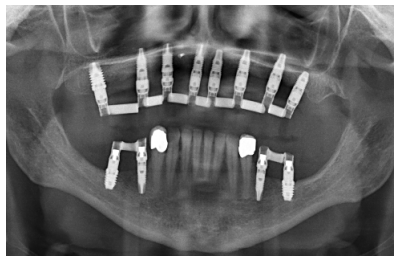

Para iniciar la fase de diagnóstico se realiza una radiografía panorámica que nos de una idea del estado general de ambos maxilares para iniciar el plan de tratamiento. En ella se ve como existe aparentemente altura en el reborde maxilar tanto a nivel anterior como posterior y un nervio dentario bajo en la mandíbula que nos permite tener una mayor cresta ósea residual disponible para la inserción de los implantes (Figura 3).

Cuatro meses después de la cirugía inicial de regeneración del maxilar se lleva a cabo un nuevo Cone-beam dental, en el que se planifica la siguiente fase de la cirugía en función de la ganancia ósea que se ha logrado con los injertos en bloque y la técnica de Split en dos fases. En las imágenes podemos observar como en las zonas de máxima atrofia, donde se colocan los bloques se ha logrado una anchura que triplica la inicial (Figuras 19 y 20). En la apertura del colgajo se observa como las imágenes del TAC de planificación se corresponden con la realidad, y además que la zona tratada mediante Split en dos fases ha logrado también una anchura de cresta que ahora permite la retirada de los implantes transicionales y la inserción de nuevos implantes en esta posición, con una mejor situación de partida y eje para la confección posterior de la prótesis (Figuras 21-22). Se procede a la inserción de los implantes y se realiza una prótesis provisional de carga progresiva apoyada en los implantes colocados en la primera fase quirúrgica. De este modo, la paciente puede tener una prótesis fija sobre implantes que servirá para ir dando forma a los provisionales en cuanto a estética y función de cara a la prótesis definitiva (Figuras 23-24).

Cuatro meses después se procede a la carga de los implantes insertados en esta segunda fase quirúrgica. De nuevo se opta por unas segundas prótesis provisionales de carga progresiva, elaboradas del mismo modo que las anteriores Tres meses después la oclusión está preparada para la confección de la prótesis definitiva, por lo que se transforma la prótesis en una prótesis metal-cerámica, atornillada sobre transepitelial confeccionada mediante cad-cam (Figuras 25-26). La paciente ha recuperado la función demandada, así como la corrección de la oclusión de la prótesis completa, que presentaba una mordida cruzada lateral derecha con disminución de la dimensión vertical al inicio del tratamiento. La paciente acude a sus revisiones y el tratamiento se mantiene estable tal como se muestra en las imágenes tomadas a los 10 años de seguimiento (Figuras 27-28).